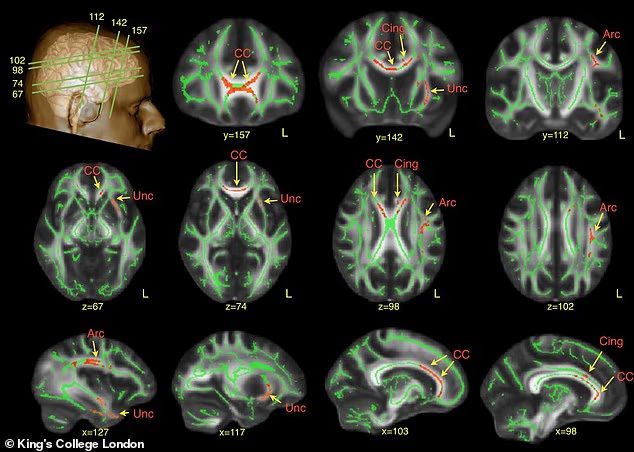

Genetics may also play a role. Studies on beagles found a mutation in the Shank3 gene—a gene linked to autism in humans. Dogs with this mutation showed reduced social interest and lower “neural synchrony,” meaning their brain activity didn’t naturally align with humans during interactions.